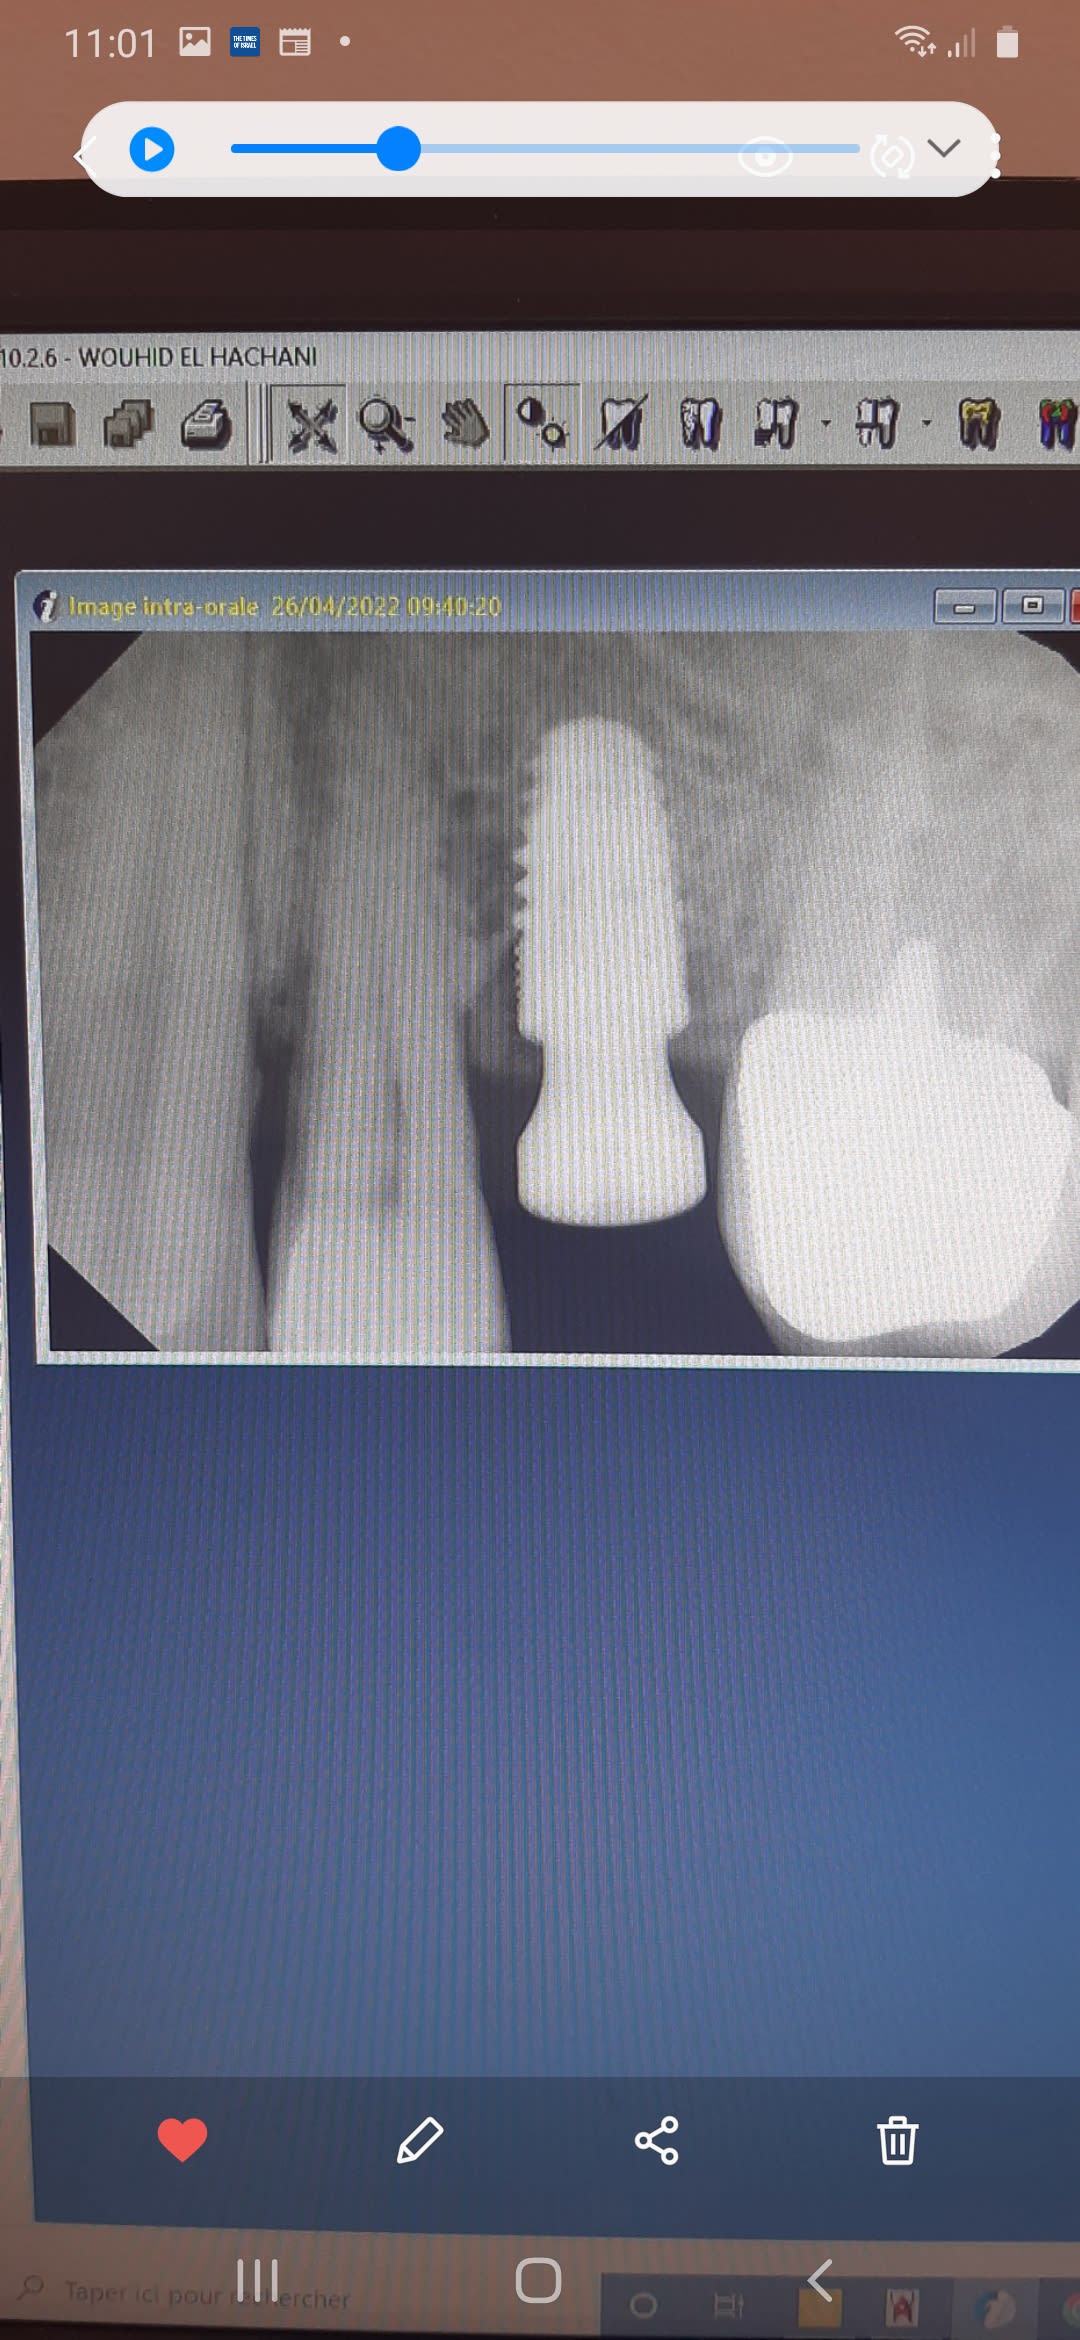

Voilà la radio ...

Sur cliniview, fichier exporter image entière jpeg, tu importes sur nonol et là il y aura assez de détails et contraste comparé à la photo pourrie de l’écran au smartphone sur laquelle on peut voir d’ailleurs le nom du patient…..

C’est pire que ça… c’est une capture d’écran de la photo d’un écran prise avec un smartphone.

Ça ressemble beaucoup à un in-kone de global D